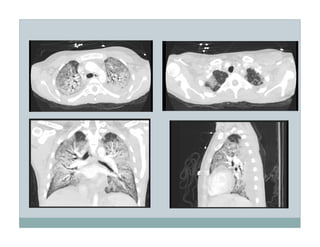

This document discusses the use of positive end-expiratory pressure (PEEP) in patients receiving mechanical ventilation. It describes a 19 year old female patient with immunosuppression and CMV pneumonia who requires intubation and mechanical ventilation. The goal of using PEEP in this patient is to decrease the risk of ventilator-induced lung injury while also aiming to increase oxygen levels and decrease the need for high oxygen supplementation. The document then reviews evidence and controversies around optimizing PEEP levels to reduce lung injury and improve outcomes in acute lung injury and acute respiratory distress syndrome patients.